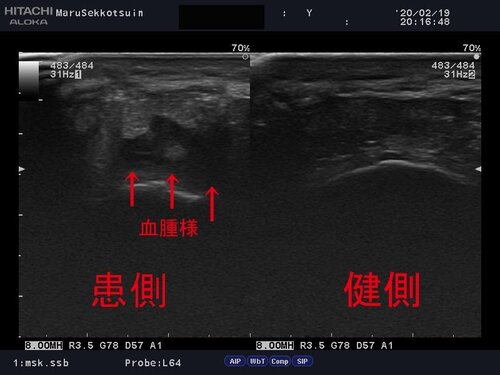

いつも通りしっかり問診、視診、触診後、確認の為、エコー検査。

結果、踵骨底面に血腫様の低エコー像があり、受傷時、強い衝撃があり、

周囲組織に損傷があった事がわかります。

痛みの原因は体重負荷時に血腫部に刺激が入り、痛みを誘発させている模様。